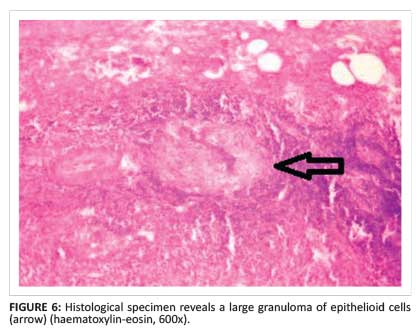

The patient subsequently underwent surgery; the lesion was completely excised along with the involved tendon sheaths. Intra-operative findings revealed characteristic melon seed bodies. A sample was sent for histopathological and polymerase chain reaction (PCR) examination. The histopathology of the resected specimen revealed granulomatous inflammation with central caseous necrosis, surrounded by epithelioid cells and multiple giant cells (Figure 6). PCR was positive for Mycobacterium tuberculosis. The patient received a full course of antituberculous chemotherapy. To date, he remains asymptomatic without any further recurrence.

Histopathological testing of the specimen reveals the granulomatous nature of the lesion. There are three histological forms of tuberculous tenosynovitis as a result of the long duration of the disease, depending upon the resistance of the individual and varying virulence of the micro-organism. In the earliest stage, the tendon is replaced by vascular granulation tissue. Later on, the sheath is obliterated by fibrous tissue. Fluid is contained within the sheath, and rice bodies may appear as a result of caseation. If healing by fibrosis fails to curtail the pathologic process, extensive caseation and granulation occur.5